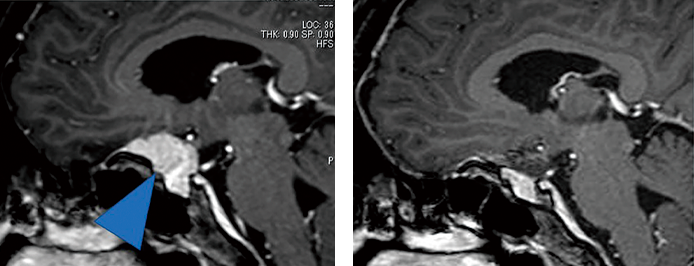

脳ドックでは、まずMRIによる脳の検査が基本となります。MRIでは脳の構造を詳しく見ることができ、同時にMRAという検査で脳や頸の血管も評価します。これらの検査を組み合わせることで、脳そのものと、それを支える血管の状態を同時に確認することができます。特に中高年以降は、脳卒中や脳腫瘍のリスクが高まるため、脳ドックの受診が重要です。

当センターの脳ドックでは、MRI(左画像)に加えてMRA(右画像)も取り入れています。MRIが得意とする脳の小さな梗塞や腫瘍のほか、くも膜下出血の原因となる脳動脈瘤や脳動脈奇形を調べることが可能となり、脳血管疾患の早期発見に強みを発揮します。